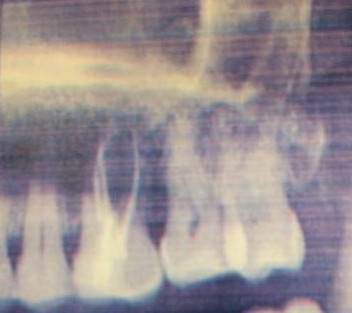

Le traitement endodontique consiste à traiter une racine dentaire. L’objectif du cabinet étant de préserver l'intégralité pulpaire, le traitement de racine ne se fait qu'un ultime recours.

Il est pratiqué lorsque la dent ne peut être conservée vivante, soit parce qu'elle est déjà nécrosée ou bien qu'elle risque de le devenir.

Sous anesthésie locale, le dentiste, près de La Varenne crée une ouverture sur la face occlusale de la dent et accède à la pulpe qu'il élimine.

A l'aide de limes et de solution antiseptique, il nettoie et désinfecte les canaux pulpaires.

Puis, après séchage, il obture les racines avec une pâte spécifique.

La dent est ensuite reconstituée soit avec une obturation coronaire si elle n'est pas trop délabrée soit avec une prothèse (couronne dentaire).